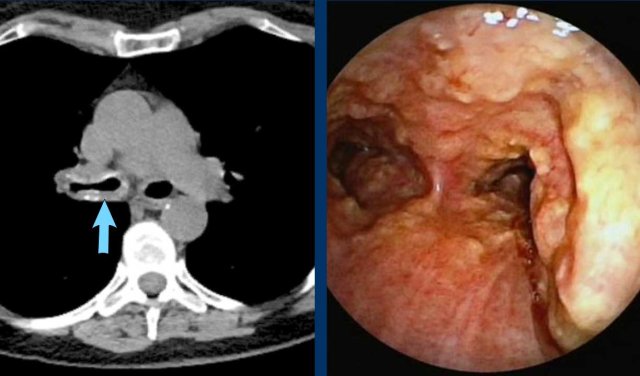

Image

Diffuse

circumferential wall thickening of the trachea and central bronchi with

uptake on FDG-PET scan (blue arrow) in a 72 y.o male after tracheostomy due to

complicated thyroidectomy.

Clinically labelled as low-grade infectious,

despite the fact that no specific pathogen was cultured.